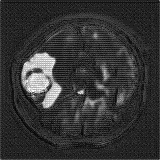

We obtain a subject-wise mean Dice score of 63.67% for the brain tumor segmentation. Utilizing a simple post-processing scheme of erosion and dilation with filter, we improve our mean Dice score to 68.01%. Figure 4 shows samples generated by our ASC-Net and Table 2 shows our before and after post-processing results. We attempted to apply f-AnoGANs [34] by following their online instructions and failed to generate good reconstructions as shown in Figure 5. The failure of AnoGANs in the reconstruction brings to light the issue with the regeneration based methods and the complexity and stability of GAN-based image reconstruction.

A most recent work in [27] trains their algorithm using 1,112 healthy scans from the Human Connectome Project (HCP) young adult dataset [38] and tests on 50 random BraTS 2018 scans, obtaining a mean dice score of 67.2% and 15.5% standard deviation. Following our simple post-processing scheme, our algorithm performs better, increasing the mean Dice score by 0.81% and reducing the standard deviation by 0.97%, on two-fold cross validation across 335 scans. Another work in [42] tests on the BraTS 2018 training set, obtaining a mean dice score of 71.63% and standard deviation of 0.84%. While their method outperforms ours, it is worth to mention that the self-supervised method is highly specialized to a particular task of tumor segmentation. It may happen that the object to be segmented is difficult to synthesize artificially or perfectly, resulting in a bottleneck of the pipeline. Furthermore, one assumption of a self-supervised learning algorithm is that the object to be learnt is known beforehand. Thus, a model trained for brain tumors cannot be applied readily to other anomalies, e.g., brain lesions. Our method, on the other hand, has no such limitations and does not need Pseudo dataset generation for a new task. That is, our method is a general approach for anomaly detection and segmentation. Also, our method performs better than [42] on the liver lesion segmentation task after post-processing.